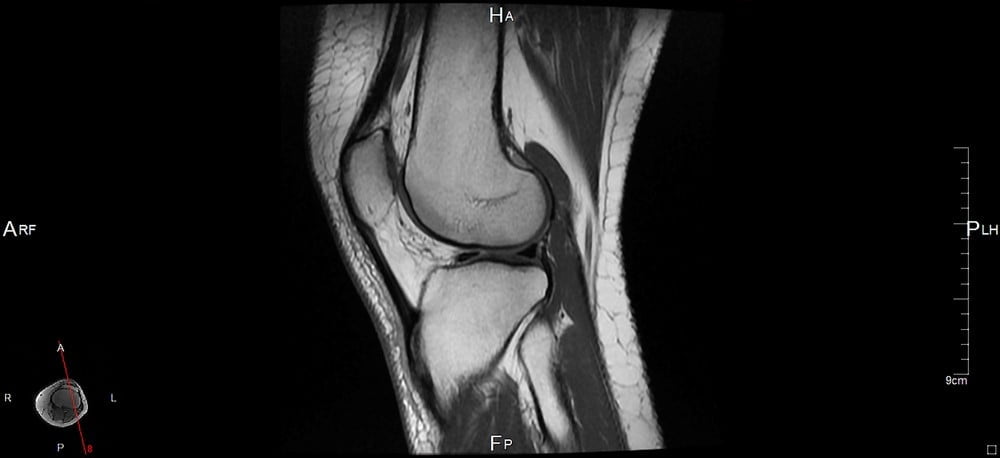

Szczególnie często wykonywany jest rezonans magnetyczny kolana, które jest jednym z największych, a zarazem najbardziej narażonych na urazy stawów.

Rezonans magnetyczny kolana do zobrazowania struktur kostnych i tkanek miękkich w obrębie stawu wykorzystuje unikalne właściwości pola magnetycznego, generowanego przez specjalistyczną aparaturę. Wzbudza ono atomy w naszych komórkach, a wysyłany przez nie sygnał odbierany jest przez specjalny detektor i za pomocą specjalnego oprogramowania przekształcany w precyzyjne obrazy. Są one bardzo dokładne i pozwalają na wykrycie nawet najmniejszych nieprawidłowości w obrębie stawów.

Co ważne, badanie jest całkowicie bezpieczne i nieinwazyjne, dzięki czemu nawet w krótkim czasie może być wykonywane wielokrotnie, bez negatywnego wpływu na zdrowie pacjenta. Po wykonaniu badania radiolog dokonuje oceny poszczególnych elementów, a także weryfikuje obecność krwawień i wysięków w obrębie jamy stawowej. W przypadku badania jakim jest rezonans magnetyczny kolana szczególnie istotna jest precyzyjna ocena więzadeł oraz zmian w chrząstkach stawowych.

Co może uwidocznić rezonans magnetyczny kolana? Przede wszystkim w wyniku badania uzyskujemy precyzyjny obraz struktury kluczowych więzadeł, tzn. więzadła krzyżowego przedniego oraz tylnego. Lekarz ma możliwość oceny nie tylko ich ciągłości, ale również położenia względem pozostałych elementów stawu. Następnie dokonywana jest ocena zbudowanych z tkanki chrzęstnej łąkotek, bocznej oraz przyśrodkowej. To właśnie nieprawidłowości w obrębie ich struktury zwykle odpowiadają za problemy z poruszaniem i bolesne dolegliwości.

Lekarz sprawdza również budowę kości oraz chrząstek stawowych. W stawie kolanowym często dochodzi w nich do uwodnienia, które powoduje stopniową destrukcję tkanek. Rezonans magnetyczny kolana odgrywa również istotną rolę w diagnostyce procesów nowotworowych. W badaniu można zobrazować zmiany nowotworowe zarówno w obrębie kości, jak i tkanek miękkich czy szpiku kostnego.